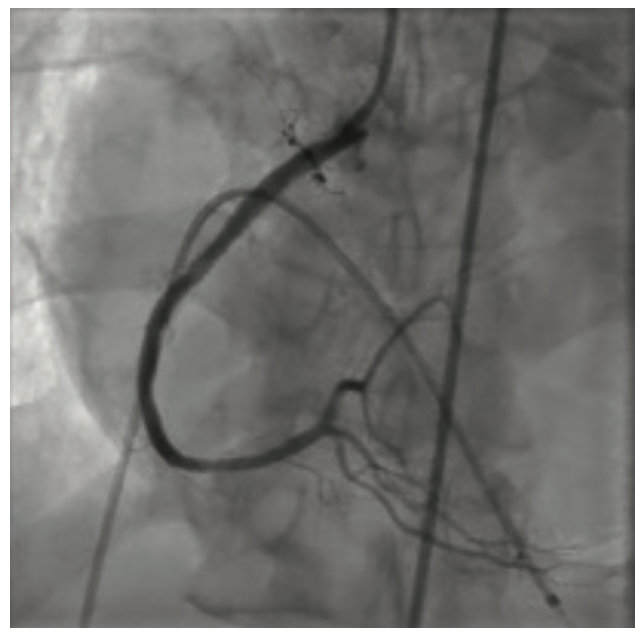

He clinically improved and on the second hospital day, underwent diagnostic cardiac catheterization. He did not have palpable radial pulses bilaterally; therefore, a femoral approach was used. His right external iliac artery and right common femoral artery were occluded. His distal aorta was heavily calcified with a high-grade eccentric stenosis. He also had a proximal 70%-80% left common iliac artery stenosis. Diagnostic coronary angiographic findings demonstrated a heavily calcified ostial 99% lesion in the right coronary artery (RCA) with significant calcium accumulation throughout the mid RCA. The left main coronary artery appeared heavily calcified, with a wedge-shaped filling defect suggesting a high-grade eccentric stenosis. The proximal left anterior descending (LAD) artery was very tortuous with a heavily calcified lesion at the first diagonal that extended into the ostium of the diagonal vessel. The circumflex artery was totally occluded. The patient’s ejection fraction based on ventriculography was 35% to 40%, with the posterior lateral wall being akinetic. He was extubated following the cardiac catheterization. Cardiothoracic surgery was consulted to provide an opinion regarding surgical revascularization. Due to his multiple comorbidities, he was felt to be high risk and not a surgical candidate. A plan for percutaneous revascularization was discussed with the patient. The nature and purpose of the procedure along with expected outcomes, together with the reasonably known risks were explained. He acknowledged that such disclosure of information had been made and that all questions asked about the procedure had been answered. He demonstrated understanding and legal capacity to consent and therefore, the written consent was obtained by his signature. The intervention was performed on hospital day 5. The patient was discharged home on hospital day 7.

The left main artery was cannulated with a 6 Fr XBLAD 3.5 guiding catheter (Cordis). The Whisper wire was used to cross the stenosis. IVUS was performed using an .014 Eagle Eye Platinum ultrasound catheter (Philips Volcano). In the same fashion as the RCA, the Whisper wire was exchanged for the ViperWire. The LM was subsequently treated with orbital atherectomy. Multiple passes were performed in opposition to the 70% nodular, calcified lesion that was fully identified on IVUS imaging. Once luminal gain was identified angiographically in the LM, the atherectomy crown was traversed distally into the calcified lesion in the proximal LAD. After two passes in the proximal LAD, the crown was traversed into the mid LAD lesion at the level of the first diagonal branch. Orbital atherectomy was again performed, reducing the calcium burden in both the LAD and the ostium of the diagonal branch. Balloon angioplasty was performed from mid LAD retrograde to the LM using a 3.0 mm x 20 mm NC Trek balloon. Following the balloon angioplasty, drug-eluting stents (3.0 mm x 15 mm Xience Skypoint, 3.5 mm x 38 mm Xience Skypoint, and a 5.0 mm x 30 mm Resolute Onyx drug-eluting stent [Medtronic], placed distal to proximal) were deployed from the mid LAD proximally to the LM, covering the orbital atherectomy-treated zone. The patient remained hemodynamically stable throughout the procedure. A completion angiogram was obtained. No slow flow or dissections were noted.